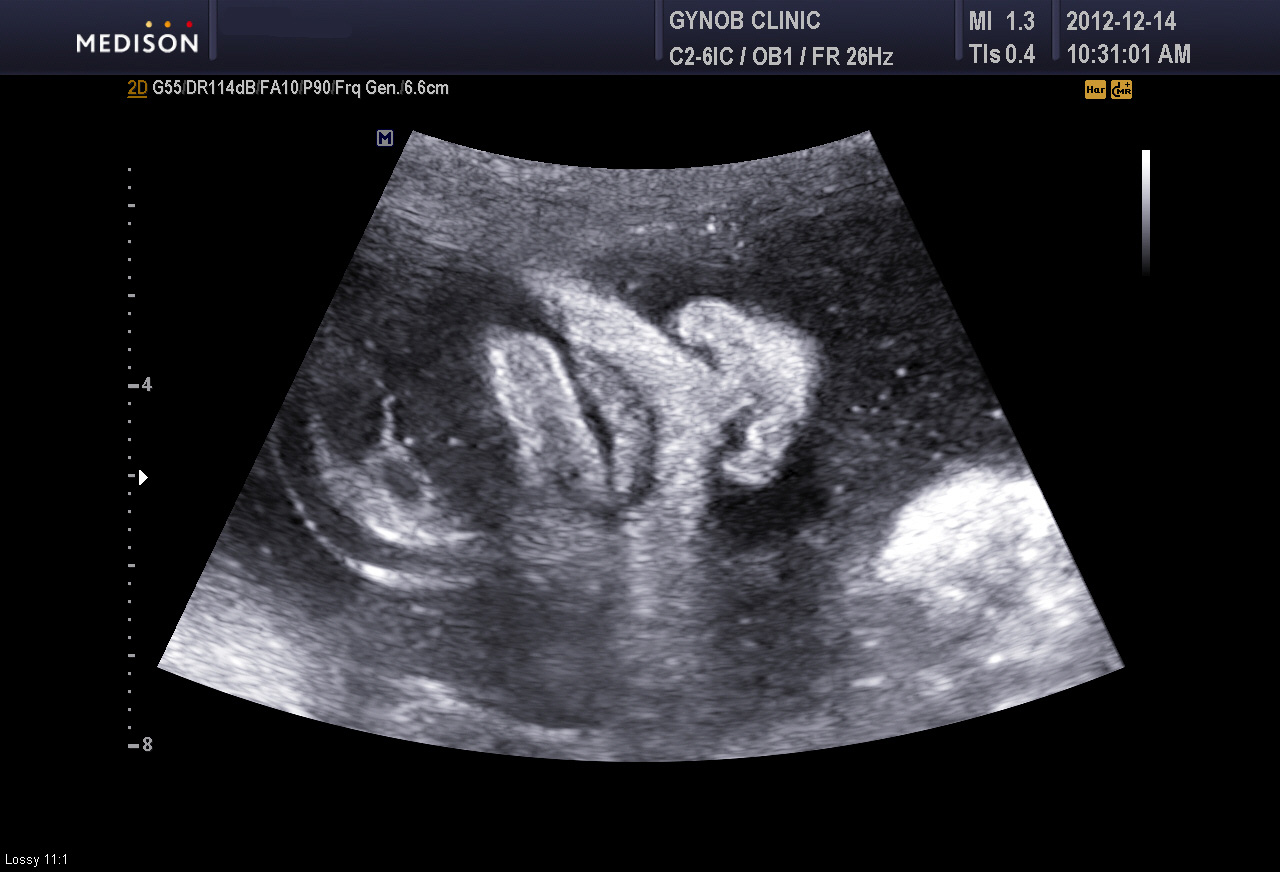

아래는 본원에서 찍은 초음파 사진으로 본 정상 태아의 입술 주변 모양입니다.

위 사진은 일반 2D 이미지 사진이고 아래는 입체 초음파 사진입니다.

구순열이 있을 경우 연속된 선이 끊어진 것으로 나타납니다.

구순열 태아의 초음파 사진을 어딘가 보관해 두었던 것 같은데 찾지 못하여 정상 사진을 올려 두는 점 양해 부탁드립니다.